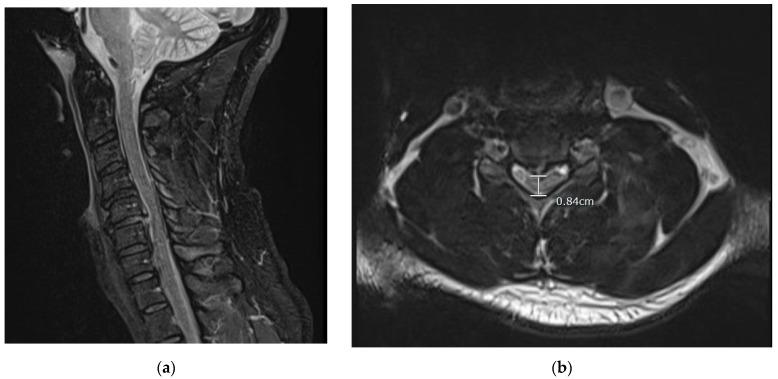

The authors report a case in which a 38-year-old male who presented himself to the emergency department with a chief complaint of cervical neck pain and paresthesia radiating from the right pectoral region down his distal right arm following self-manipulation of the patient's own cervical vertebrae. Initial emergency department imaging via cervical x-ray and magnetic resonance imaging (MRI) without contrast revealed no cervical fractures; however, there was evidence of an acute cervical disc herniation (C3-C7) with severe herniation and spinal stenosis located at C5-C6. Immediate discectomy at C5-C6 and anterior arthrodesis was conducted in order to decompress the cervical spinal cord. Acute traumatic cervical disc herniation is rare in comparison to disc herniation due to the chronic degradation of the posterior annulus fibrosus and nucleus pulposus. Traumatic cervical hernias usually arise due to a very large external force causing hyperflexion or hyperextension of the cervical vertebrae. However, there have been reports of cervical injury arising from cervical spinal manipulation therapy (SMT) where a licensed professional applies a rotary force component. This can be concerning, considering that 12 million Americans receive SMT annually (Powell, F.C.; Hanigan, W.C.; Olivero, W.C. A risk/benefit analysis of spinal manipulation therapy for relief of lumbar or cervical pain. , , 73-79.). This case study involved an individual who was able to apply enough rotary force to his own cervical vertebrae, causing severe neurological damage requiring surgical intervention. Individuals with neck pain should be advised of the complications of SMT, and provided with alternative treatment methods, especially if one is willing to self manipulate.

作者报告了一例病例,一名38岁男性因自行推拿颈椎后出现颈部疼痛和从右胸区域向下放射至右上肢远端的感觉异常为主诉前来急诊科就诊。急诊科最初通过颈椎X线和无造影剂的磁共振成像(MRI)检查未发现颈椎骨折;然而,有证据显示存在急性颈椎间盘突出(C3 - C7),其中C5 - C6处有严重突出及椎管狭窄。随即对C5 - C6进行了椎间盘切除术及前路椎间融合术,以减压颈脊髓。与因纤维环后部和髓核慢性退变导致的椎间盘突出相比,急性创伤性颈椎间盘突出较为罕见。创伤性颈椎间盘突出通常是由于非常大的外力导致颈椎过度前屈或后伸引起的。然而,有报告称颈椎脊柱推拿疗法(SMT)(有执照的专业人员施加旋转力成分)可导致颈部损伤。鉴于每年有1200万美国人接受SMT(鲍威尔,F.C.;哈尼根,W.C.;奥利韦罗,W.C. 脊柱推拿疗法缓解腰或颈疼痛的风险/效益分析。 , ,73 - 79.),这可能令人担忧。本病例研究涉及一名能够对自己的颈椎施加足够旋转力,导致严重神经损伤并需要手术干预的个体。对于颈部疼痛的个体,应告知其SMT的并发症,并提供替代治疗方法,尤其是对于那些愿意自行推拿的人。